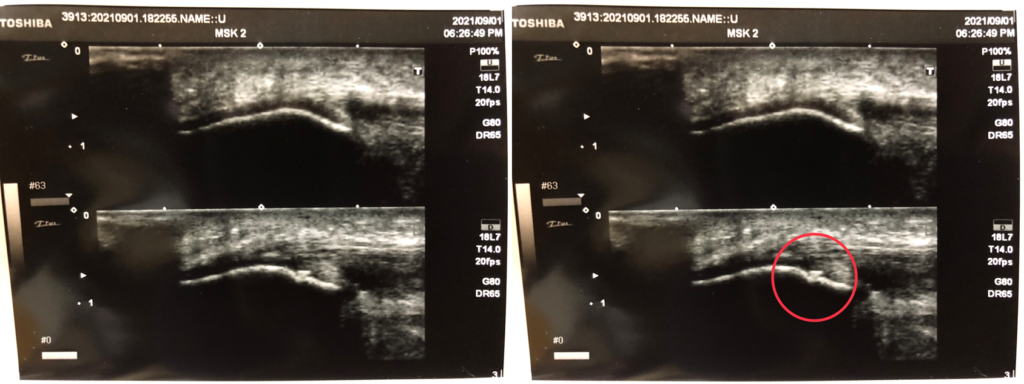

国は、柔道整復師が業務の中で超音波エコー観察機器を使い、損傷の評価や程度を対応の参考情報にすることは、差し支えないと、正式に見解を出している。

もし、骨折や脱臼等の重傷症状の場合は、超音波エコー画像が応急手当への参考情報となる。

※なお、ねんざや、打撲、肉離れ、筋腱の断裂などは、超音波エコー観察検査を実施した上、柔道整復師自身の判断で治療が行えます。